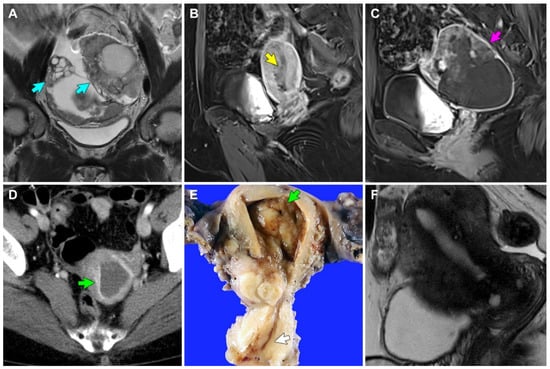

| Imaging finding | 8.6-cm solid and cystic bilateral ovarian masses; borderline-sized pelvic and retroperitoneal lymph nodes; peritoneal carcinomatosis | 8.6-cm solid and cystic left ovarian mass; 3.4-cm EM mass; enlarged retroperitoneal lymph nodes; peritoneal carcinomatosis | 1-cm EM mass; no lymph node enlargement; no peritoneal seeding | No identifiable EM lesion; no lymph node enlargement; no peritoneal seeding |

| Clinical impression | Ovarian cancer | Concurrent ovarian and EM cancers | EM cancer | MRI-invisible EM cancer |

| Final pathological diagnosis | Stage IIIC grade 3 EC (ovary) | Stage IIIC grade 3 EC (ovary); stage IB grade 1 EC (EM) | Stage IA grade 1 EC (EM) | Stage IA grade 1 EC (EM) |

| Greatest dimension of ECP | 17 mm | 19 mm | 11 mm | 16 mm |

| Greatest dimension of EC | 6 mm | 3 mm | 4 mm | 10 mm |

| Invasion depth into polyp stroma | 1 mm | 0.3 mm | 0.3 mm | 1 mm |